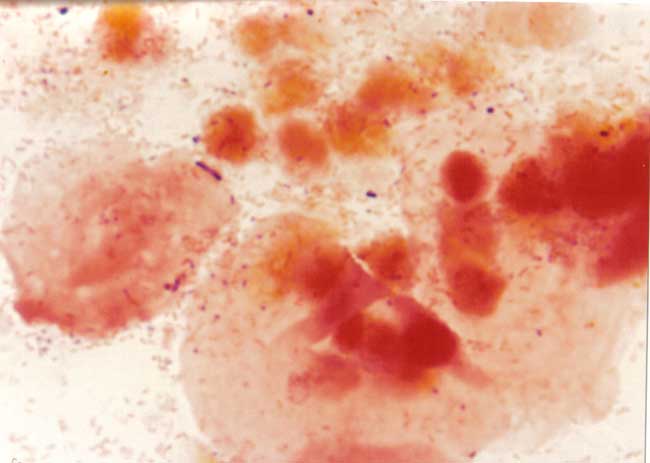

La vaginosis bacteriana es una condición en la que se altera el equilibrio normal de los microorganismos que se encuentran naturalmente en la vagina. Esta alteración de la flora vaginal se produce cuando las bacterias que son útiles y se reducen más las bacterias dañinas se incrementan. Además de aumentar el riesgo de infectarse con el VIH, la vaginosis bacteriana puede aumentar el riesgo de contraer otras infecciones de transmisión sexual y aumentar el riesgo de parto prematuro. Además, las mujeres infectadas con este trastorno pueden tener niveles más altos y una mayor eliminación del virus del cuello del útero y la vagina.

vaginosis bacteriana, vaginosis bacteriana virus, vaginosis y vih, mujeresdesesentaconvih, imagenes de vaginosis bacteriana, vagina con vih